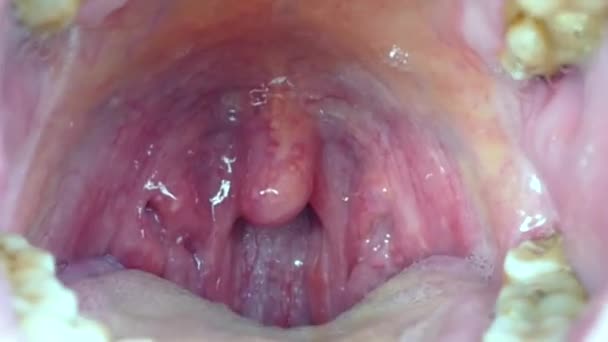

Тонзиллит — это воспалительный процесс в миндалинах . Недуг может носить острый характер и хронический . Острая форма больше известна как ангина . При хронической — периоды обострения (воспаление миндалин) сменяется периодом ремиссии (затишья) . Чаще всего заболевание встречается у детей 5-15 лет, хотя заболеванию подвержены и взрослые .

Миндалины подразделяются на: парные . нёбные — в углублении между мягким нёбом и языком (первая и вторая миндалины); трубные — в области глоточного отверстия слуховой трубы (пятая и шестая миндалины) .

Глоточная миндалина — непарная, располагается в верхнезадней части глотки . Она покрыта многорядным столбчатым реснитчатым эпителием, типичным для дыхательного тракта, хотя выявляются также и участки многослойного эпителия . Глоточная миндалина состоит из складок слизистой оболочки и содержит диффузную лимфоидную ткань и лимфоидные узелки .

Строение и функции миндалин Миндалины - важная и необходимая составляющая иммунной системы . Они первыми встречают и дают отпор микробам, попадающим в организм из внешней среды .Миндалины представляют собой . . .

В ткани миндалины происходит размножение и созревание иммунных клеток - лимфоцитов, отвечающих за выработку защитных антител и уничтожение чужеродных микроорганизмов . Внутренняя полость ее омывается лимфой, так как она сообщается с лимфатическими сосудами и является частью иммунной системы .